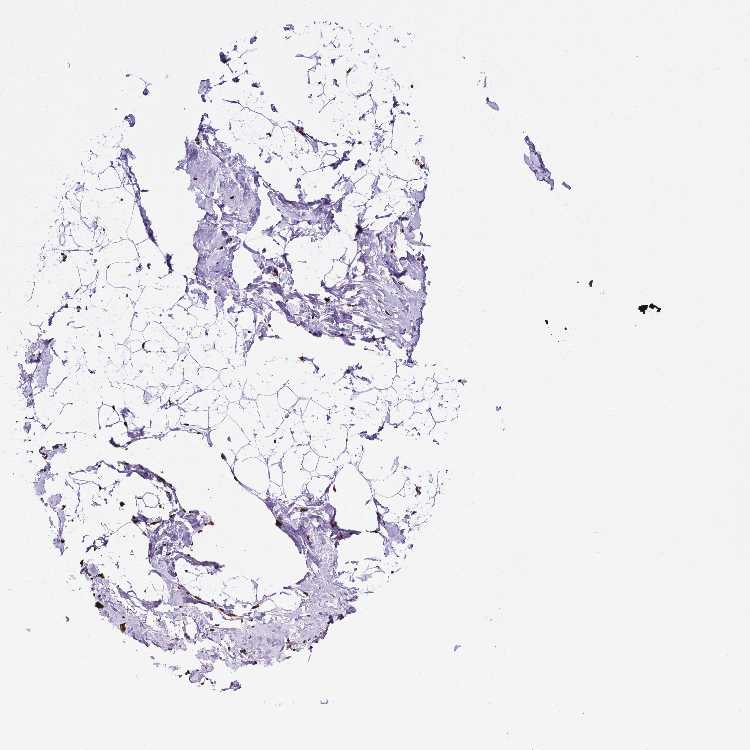

BREAST - Antibody stainingi

Antibody staining in the annotated cell types in the current human tissue is reported as not detected, low, medium, or high, based on conventional immunohistochemistry profiling in selected tissues. This score is based on the combination of the staining intensity and fraction of stained cells.

Each image is clickable and will lead to virtual microscopy that enables deeper exploration of all samples and also displays staining intensity scores, fraction scores and subcellular localization as well as patient and tissue information for each sample.

Antibody HPA071268

Adipocytes Medium

Glandular cells High

Myoepithelial cells High